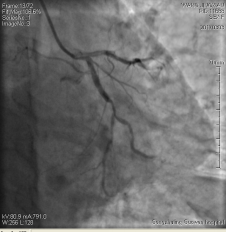

3月3日14時30分:經(jīng)右橈動脈行冠脈造影見:左主干未見明顯異常,TIMI血流3級,前降支開口正常,近中段20%狹窄,TIMI血流3級;回旋支開口正常,中遠段75%狹窄,TIMI血流3級。右冠狀動脈開口正常,中段長病變,最重99%狹窄, TIMI血流3級。

圖1 回旋支遠段70%狹窄 圖2 右冠脈中段99%狹窄